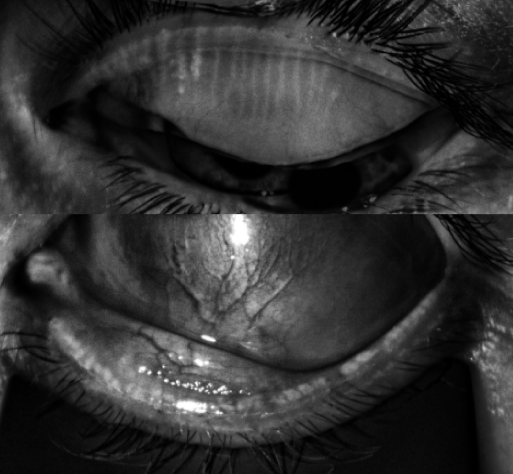

The below is his right eye. He has some Meibomian glands left in the right upper lid and only little stumps left in the right lower lid.

The left eye below is worse: he has almost nothing left in the left upper lid and lower lid.